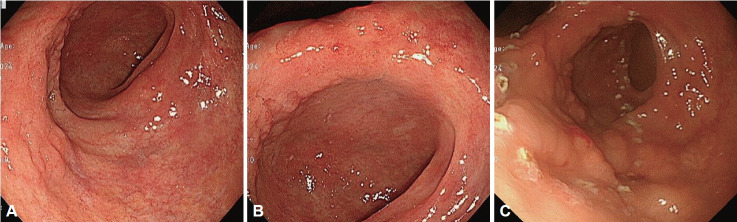

Endoscopic submucosal dissection (ESD) has emerged as a standard minimally invasive treatment for early gastric cancer and precancerous lesions. However, extensive resection near the pyloric ring or antrum can lead to post-ESD gastric outlet obstruction (GOO) due to cicatricial stenosis and luminal deformation. This report presents a case of a 79-year-old man who developed severe GOO following ESD for an antral tubular adenoma with low-grade dysplasia. Initial management with endoscopic antralplasty and local triamcinolone injection failed to provide sustained symptomatic relief. As a salvage therapy, a partially covered self-expandable metallic stent (SEMS) was placed across the antrum, pyloric ring, and proximal duodenum. This intervention resulted in complete resolutions of obstructive symptoms and restoration of normal oral intake. The SEMS was successfully removed after 4 weeks with no recurrence of GOO symptoms thereafter. This case highlights the therapeutic challenges of post-ESD GOO and demonstrates that SEMS placement is a viable salvage treatment for refractory cases. Further studies are required to optimize treatment strategies and assess long-term outcomes.